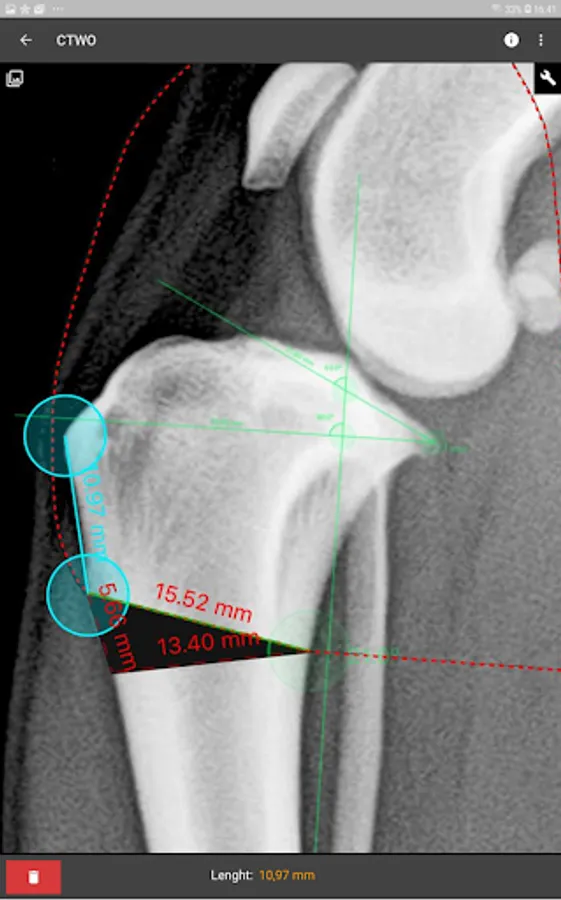

e) Wedge cut, CTWO and angular osteotomies.

l) CTWO plates